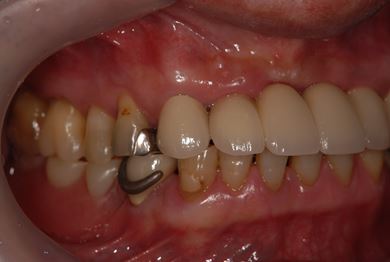

インプラントの症例写真 IMPLANT

骨再生スピードインプラント治療+セラミック治療

| 治療方針 | 上前歯部は、抜歯と同時にインプラントを埋入し、治療期間を短縮する。左上奥は、ソケットリフトにて上顎洞を拳上し、インプラント治療を可能にする。 | ||||||||||||||||||||||||||||||||

| 治療内容 | インプラント4本(ソケットリフト・抜歯即日)、テンポラリーインプラント2本、メタルボンドクラウン9本 | ||||||||||||||||||||||||||||||||